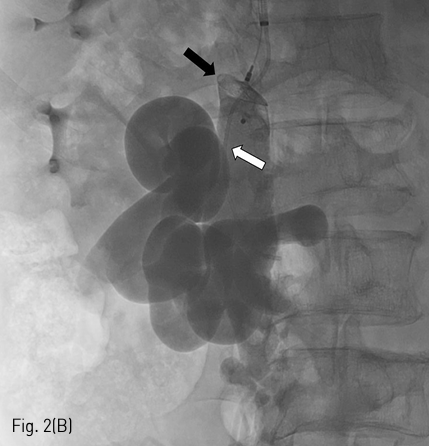

Fig 2B

(B) After vascular plug (black arrow) placement in narrowest portion of the meso-caval shunt, additional embolization of the meso-caval shunt and mesenteric-retroperitoneal varices was performed using gelatin sponges through the 4-F catheter (white arrow).